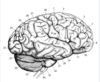

Key gyri on superior view of frontal cortex

Superior frontal gyrus

Middle frontal gyrus

Inferior frontal gyrus

Precentral gyrus

Key sulci on superior view of frontal lobe

Superior frontal sulcus

Inferior frontal sulcus

Precentral sulcus

Key gyri on medial view of frontal lobe

Paracentral lobule

Cingulate gyrus

Key sulci on medial surface of frontal lobe

Cingulate sulcus